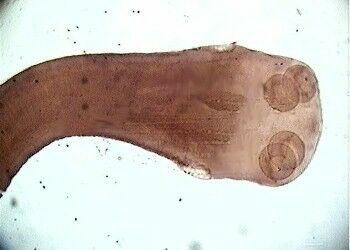

Osiąga 2–4 m i może mieć do 1000 członów. Ogólna budowa jego ciała jest podobna do budowy innych tasiemców. Pasożytuje również w jelicie cienkim. Swoistą cechą charakterystyczną jest to, że główka, poza 4 przyssawkami, ma jeszcze uzbrojenie dodatkowe wzmocnione podwójnym wieńcem haczyków, którymi bardzo silnie przyczepia się do błony śluzowej jelita żywiciela. Człowiek jest jedynym żywicielem ostatecznym tego tasiemca.